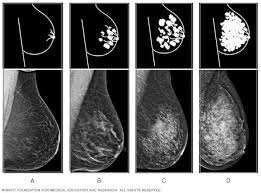

Breast Masses Cancerous Tumor Or Benign Lump from www.verywellhealth.com Even if you have a lump in only one breast, pictures will be taken of both breasts. This appears most commonly as streaking, known as linear enhancement. A woman's breast tissue also changes over time, and it is not uncommon for benign lumps, cysts or calcifications to form with age. Breast cancer can appear as a spiculated mass, cluster of tiny calcifications, smoothly marginated mass, area of subtle distortion or be invisible on. What does an abnormal mammogram look like? Cancer cells can remain within the milk ducts and this is considered as noninvasive cancer or ductal carcinoma in situ. Magnetic resonance imaging (mri) of the breast — or breast mri — is a test used to detect breast cancer and other abnormalities in the breast. The appearance of normal breast tissue on a mammogram varies from person to person, and no two mammograms look the same.

Breast Cancer Ge News from www.ge.com Healthy mammograms can still vary in appearance. The dye collection in the breast can also look clumpy or appear in a section of the breast, depending on the involvement of dcis. It can also be used to investigate the cause of breast problems, such as a breast mass, pain and nipple. Cancers may be seen as masses (like a ball, but usually with an irregular shape), areas of asymmetry that resemble normal tissue, calcifications (white specks), and/or areas of architectural distortion (imagine the puckering caused by pulling a thread in a piece of fabric). There are few risks associated with mammography. If you've had a mammogram before, the radiologist should compare your old mammogram to the new one to look for changes. After a mammogram that didn't show anything, and a sonogram that found the lump, i was diagnosed with stage 2 breast cancer. The doctor reading your mammogram will be looking for different types of breast changes, such as small white spots called calcifications, larger abnormal areas called masses, and other suspicious areas that could be signs of cancer.

Mammogram Images Normal And Abnormal from www.verywellhealth.com Any area that does not look like normal tissue is a possible cause for concern. The appearance of normal breast tissue on a mammogram varies from person to person, and no two mammograms look the same. A woman's breast tissue also changes over time, and it is not uncommon for benign lumps, cysts or calcifications to form with age. What does cancer look like on a mammogram? Tumors may be benign or cancerous. Abnormalities such as cancerous tumors usually appear brighter because they are denser. Cancers may be seen as masses (like a ball, but usually with an irregular shape), areas of asymmetry that resemble normal tissue, calcifications (white specks), and/or areas of architectural distortion (imagine the puckering caused by pulling a thread in a piece of fabric). Calcifications are calcium deposits within the breast tissue and they look like small white spots.